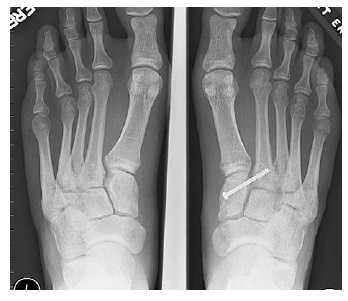

Отдельно стоит разобрать тему разрыва связки Лисфранка с изолированной нестабильностью 2 предплюсне-плюсневого сустава. Частота данного повреждения значительно выросла за последние 50 лет в связи с популяризацией спорта. Также крайне высота частота отсроченной постановки диагноза. При этой патологии пациента беспокоит боль по тыльной поверхности 1-2-3 предплюсне-плюсневых суставов при физической нагрузке. Часто при осмотре удаётся обнаружить деформацию в данной области. Если осмотр производится отсрочено через несколько недель или месяцев после травмы то клинически определить нестабильность уже не удастся, однако на рентгенограммах с нагрузкой будет виден диастаз между медиальной клиновидной костью и основанием 2 плюсневой кости.

В случаях этого повреждения показано оперативное лечение, открытое устранение подвывиха основания 2 плюсневой кости с фиксацией винтом. Устранение подвывиха производится из доступа в 1 межплюсневом промежутке, рубцовая ткань и остатки связки могут интерпонировать сустав, тогда потребуется их удалить. После вправления производится предварительная фиксация спицей и рентгенологический контроль.

Затем устанавливается винт соединяющий основание 2 плюсневой кости и медиальную клиновидную кость.

![как лечить вывих стопы]()

После операции следует 6-12 недельный период иммобилизации в жёстком ортезе без осевой нагрузки на ногу. Затем нагрузка постепенно увеличивается до полной в течение 4-6 недель.

Данный метод оперативного лечения эффективен в течение первых 6-8 месяцев после травмы. В случае если с момента травмы прошло больше времени целесообразно выполнение артродеза.

Удаление винта производится через 6-12 месяцев после операции. В случае формирования болезненного посттравматического артрита 2 предплюсне-плюсневого сустава также показано выполнение его артродеза.